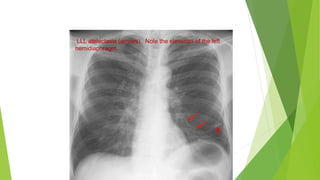

Indirect signs

These include:

† Elevation of a hemi-diaphragm. This sign is of limited value as

the normal position of the diaphragm is variable.

† Mediastinal displacement to the side of collapse. Some contents

of the mediastinum which are easily seen on plain chest X-rays

include the trachea, tracheal tube, central venous catheters in the

superior vena cava, and nasogastric tubes in the oesophagus.

† Hilar displacement. The hilum may be elevated in the upper lobe

collapse, and depressed in the lower lobe collapse.

LLL atelectasis (arrows). Note the elevation of the left

hemidiaphragm.